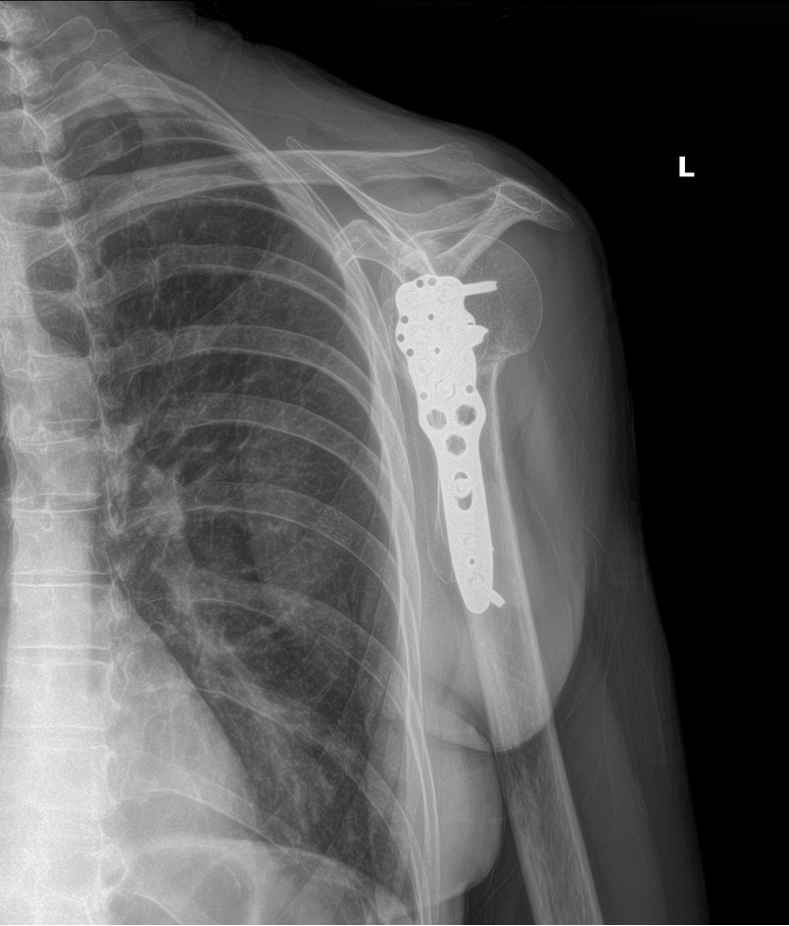

Unfortunately, over the next couple of weeks Mrs. A’s shoulder pain got worse. The doctor ordered more x-rays, which showed that the broken bone was now out of alignment. He informed Mrs. A that she would now need surgery to repair the fracture. She underwent the surgery, called an open reduction internal fixation surgery. It involved using a metal plate and screws to secure the fracture and correctly align it while it healed. Here are x-rays of her shoulder after the surgery: